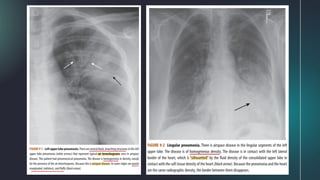

1. Right Upper Lobe Atelectasis

A. Frontal radiograph:

● upward shift of the minor fissure

● rightward shift of the trachea

● combination of a hilar mass and the

upward shift of the minor fissure

produces S sign of Golden

B. Lateral radiograph:

● forward shift of the major fissure